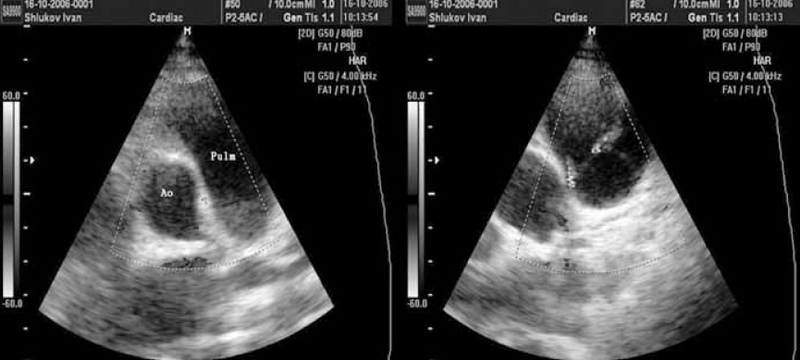

В подавляющем большинстве случаев сброс крови из аорты в легочную артерию через ОАП визуализируется в стволе легочной артерии как поток красного спектра, направленный к датчику в левой парастернальной позиции по короткой оси (см. рис. 2). Сложности эхокардиографической диагностики и дифференциальной диагностики ОАП у детей могут быть обусловлены наличием других разнонаправленных потоков, визуализируемых в стволе легочной артерии, особенно в режиме цветового допплеровского картирования (рис. 3–6). Часть из них направлена «к датчику» и окрашивается в красные цвета, другие направлены «от датчика» и визуализируются как потоки синего цвета. Таким образом, высокоскоростные патологические потоки из аорты в легочную артерию через открытый артериальный проток и аортолегочную фистулу имеют направление «к датчику» и окрашиваются в цвета красного спектра. Низкоскоростные потоки из бассейна коронарных артерий в легочную артерию через коронарные фистулы чаще окрашиваются в синие цвета «от датчика» (см. рис. 3–5).

Рис. 3. Эхокардиограммы выполнены из левого парастернального доступа по короткой оси. В зоне интереса ствол легочной артерии в режиме цветного допплеровского картирования. Слева и справа визуализируется поток из коронарной фистулы (предположительно бассейн левой коронарной артерии) в ствол легочной артерии. При цветном допплеровском картировании аномальный поток окрашен в синий цвет, движение «от датчика»

Рис. 4. Эхокардиограммы выполнены из левого парастернального доступа по короткой оси. В зоне интереса ствол легочной артерии в режиме цветного допплеровского картирования. Слева визуализирована зона бифуркации ствола легочной артерии на правую и левую ветви. На правой эхограмме визуализируется поток из коронарной фистулы (бассейн левой коронарной артерии) в ствол легочной артерии. При цветном допплеровском картировании аномальный поток окрашен в синий цвет, движение «от датчика»

Рис. 5. Эхокардиограммы выполнены из левого парастернального доступа по короткой оси. В зоне интереса восходящая аорта и ствол легочной артерии в режиме цветного допплеровского картирования. Слева визуализирована фистула небольших размеров между аортой и стволом легочной артерии. На правой эхограмме визуализируется поток через фистулу/свищ из аорты в ствол легочной артерии

Диастолический сброс крови через коронарную фистулу в легочную артерию при постоянно-волновом допплеровском картировании отчасти напоминает аналогичный сброс через ОАП, однако является более низкоскоростным и менее продолжительным по времени, не занимая весь диастолический промежуток на допплерограмме (см. рис. 6).